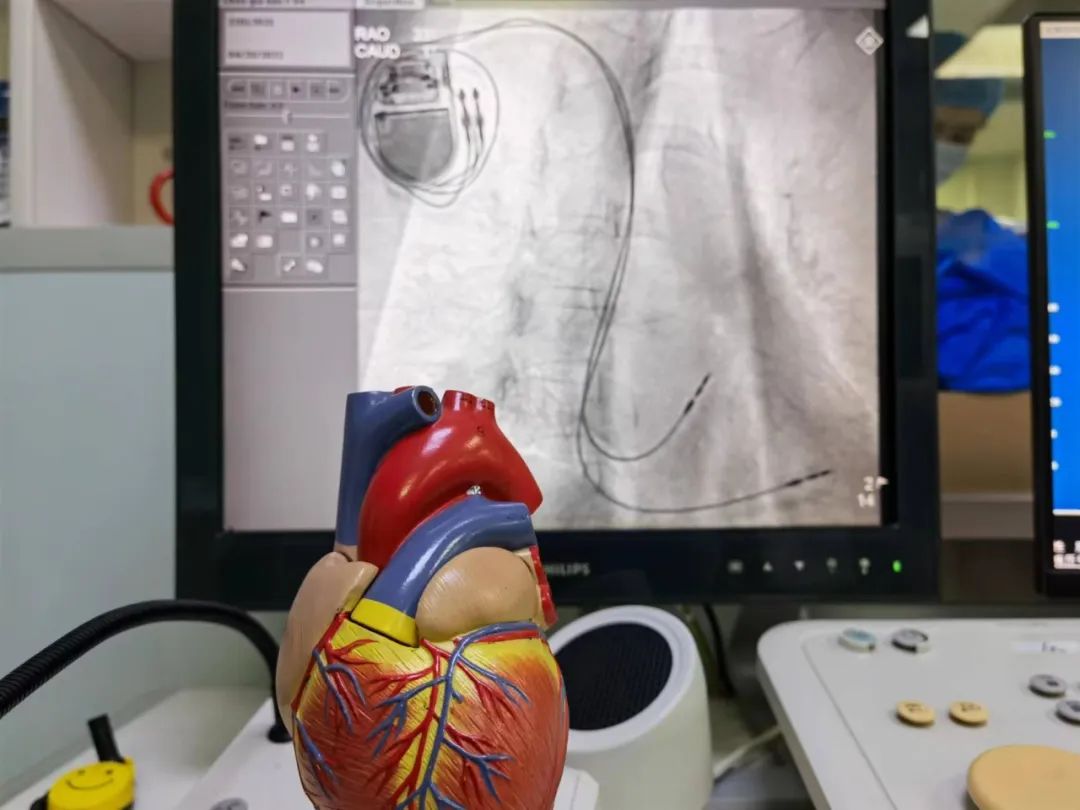

4月19日,包医一附院成功为一名病态窦房结综合征患者植入兼容磁共振的心脏起搏器。这也是医院首个纳入“集采”的抗核磁起搏器,极大降低了患者经济负担。

随后,经过细致的术前规划,蔺雪峰团队为该患者实施了手术,手术历经50分钟,术后患者恢复良好。